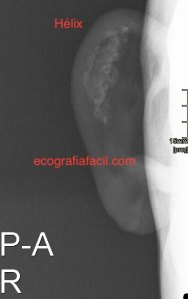

En la imagen 4 tienes la radiografía de la oreja donde puedes ver claramente la calcificación que ocupa parte importante del pabellón auricular. Con la radiografía se entiende todo mucho mejor porque es una patología que no suele verse muy habitualmente. La Rx simple clarificó el diagnóstico y ayudó a entender lo que se vio en la imagen ecográfica.

Consultado el Radiólogo que realizó el informe, me aporta que este tipo de patología pudiera tener origen traumático, calcificando un posible hematoma tras un golpe, el paciente me aseguró no tener antecedente traumático. También me comenta la posibilidad de ser de origen metabólico, aunque curiosamente me dijo que existe una gran cantidad de patología que pueden originar este curioso patrón ecográfico.

La calcificación del cartílago auricular puede seguir a la evolución de la Policondritis Recidivante. No lo había visto nunca por eco pero sí en Rx y TAC. Debido a los contínuos golpes del pabellón auricular durante la lucha canaria (los pabellones auriculares rozan y sufren microtraumatismos al contacto con la arenilla) es típica la calcificación distrófica del pabellón auricular en este deporte: «Oreja de la lucha canaria». Descrita en varones, si bien ahora la lucha canaria, deporte vernáculo de las islas Canarias, empiezan a practicarlo las mujeres. Suele ser asimétrica, ya que cada luchador tiende a caer siempre sobre el mismo lado. Imágenes similares se ven en otros deportes marciales (oreja en coliflor). Muchas gracias por vuestra actividad. Saturnino Suárez Ortega. Las Palmas de Gran Canaria. ________________________________